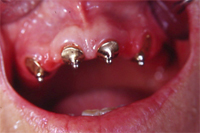

Seit neun Jahren trägt die jetzt 74 Jahre alte Frau im Oberkiefer eine Prothese, die über vier Druckknöpfe (Abb. 1) auf vier eigenen Frontzähnen gut stabilisiert und fixiert ist. Die Patientin ist mit der Lösung, die ich ihr im Jahre 1996 gemacht habe, ästhetisch und funktionell total zufrieden.